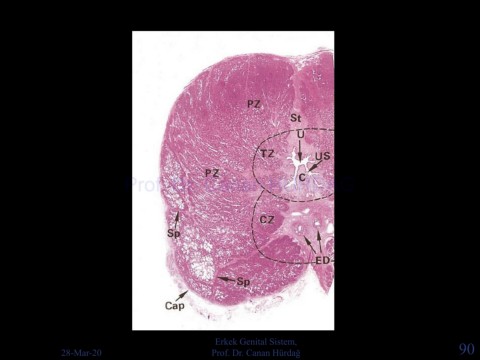

Page 90 - Erkek Genital Sistemi

Erkek Genital Sistem,